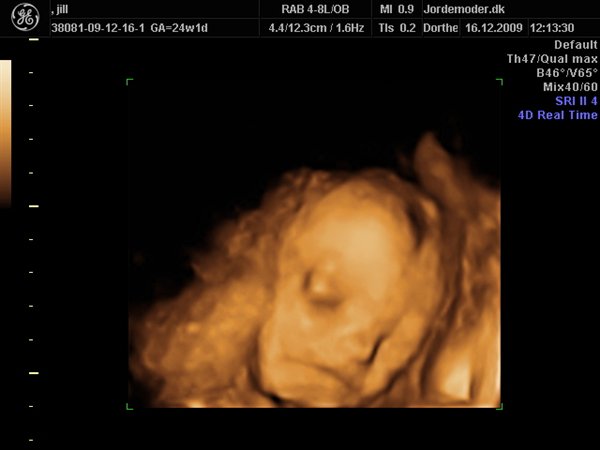

her er lidt fra vores scanning i uge 24+1, hun blev vurderet til 675 g....jeg synes det er vildt så mange detaljer og ansigsudtryk hun havde;-)

derfor glæder jeg mig til at se hende "rigtigt"....synes hun ligner mig som baby...hehe

knus jill